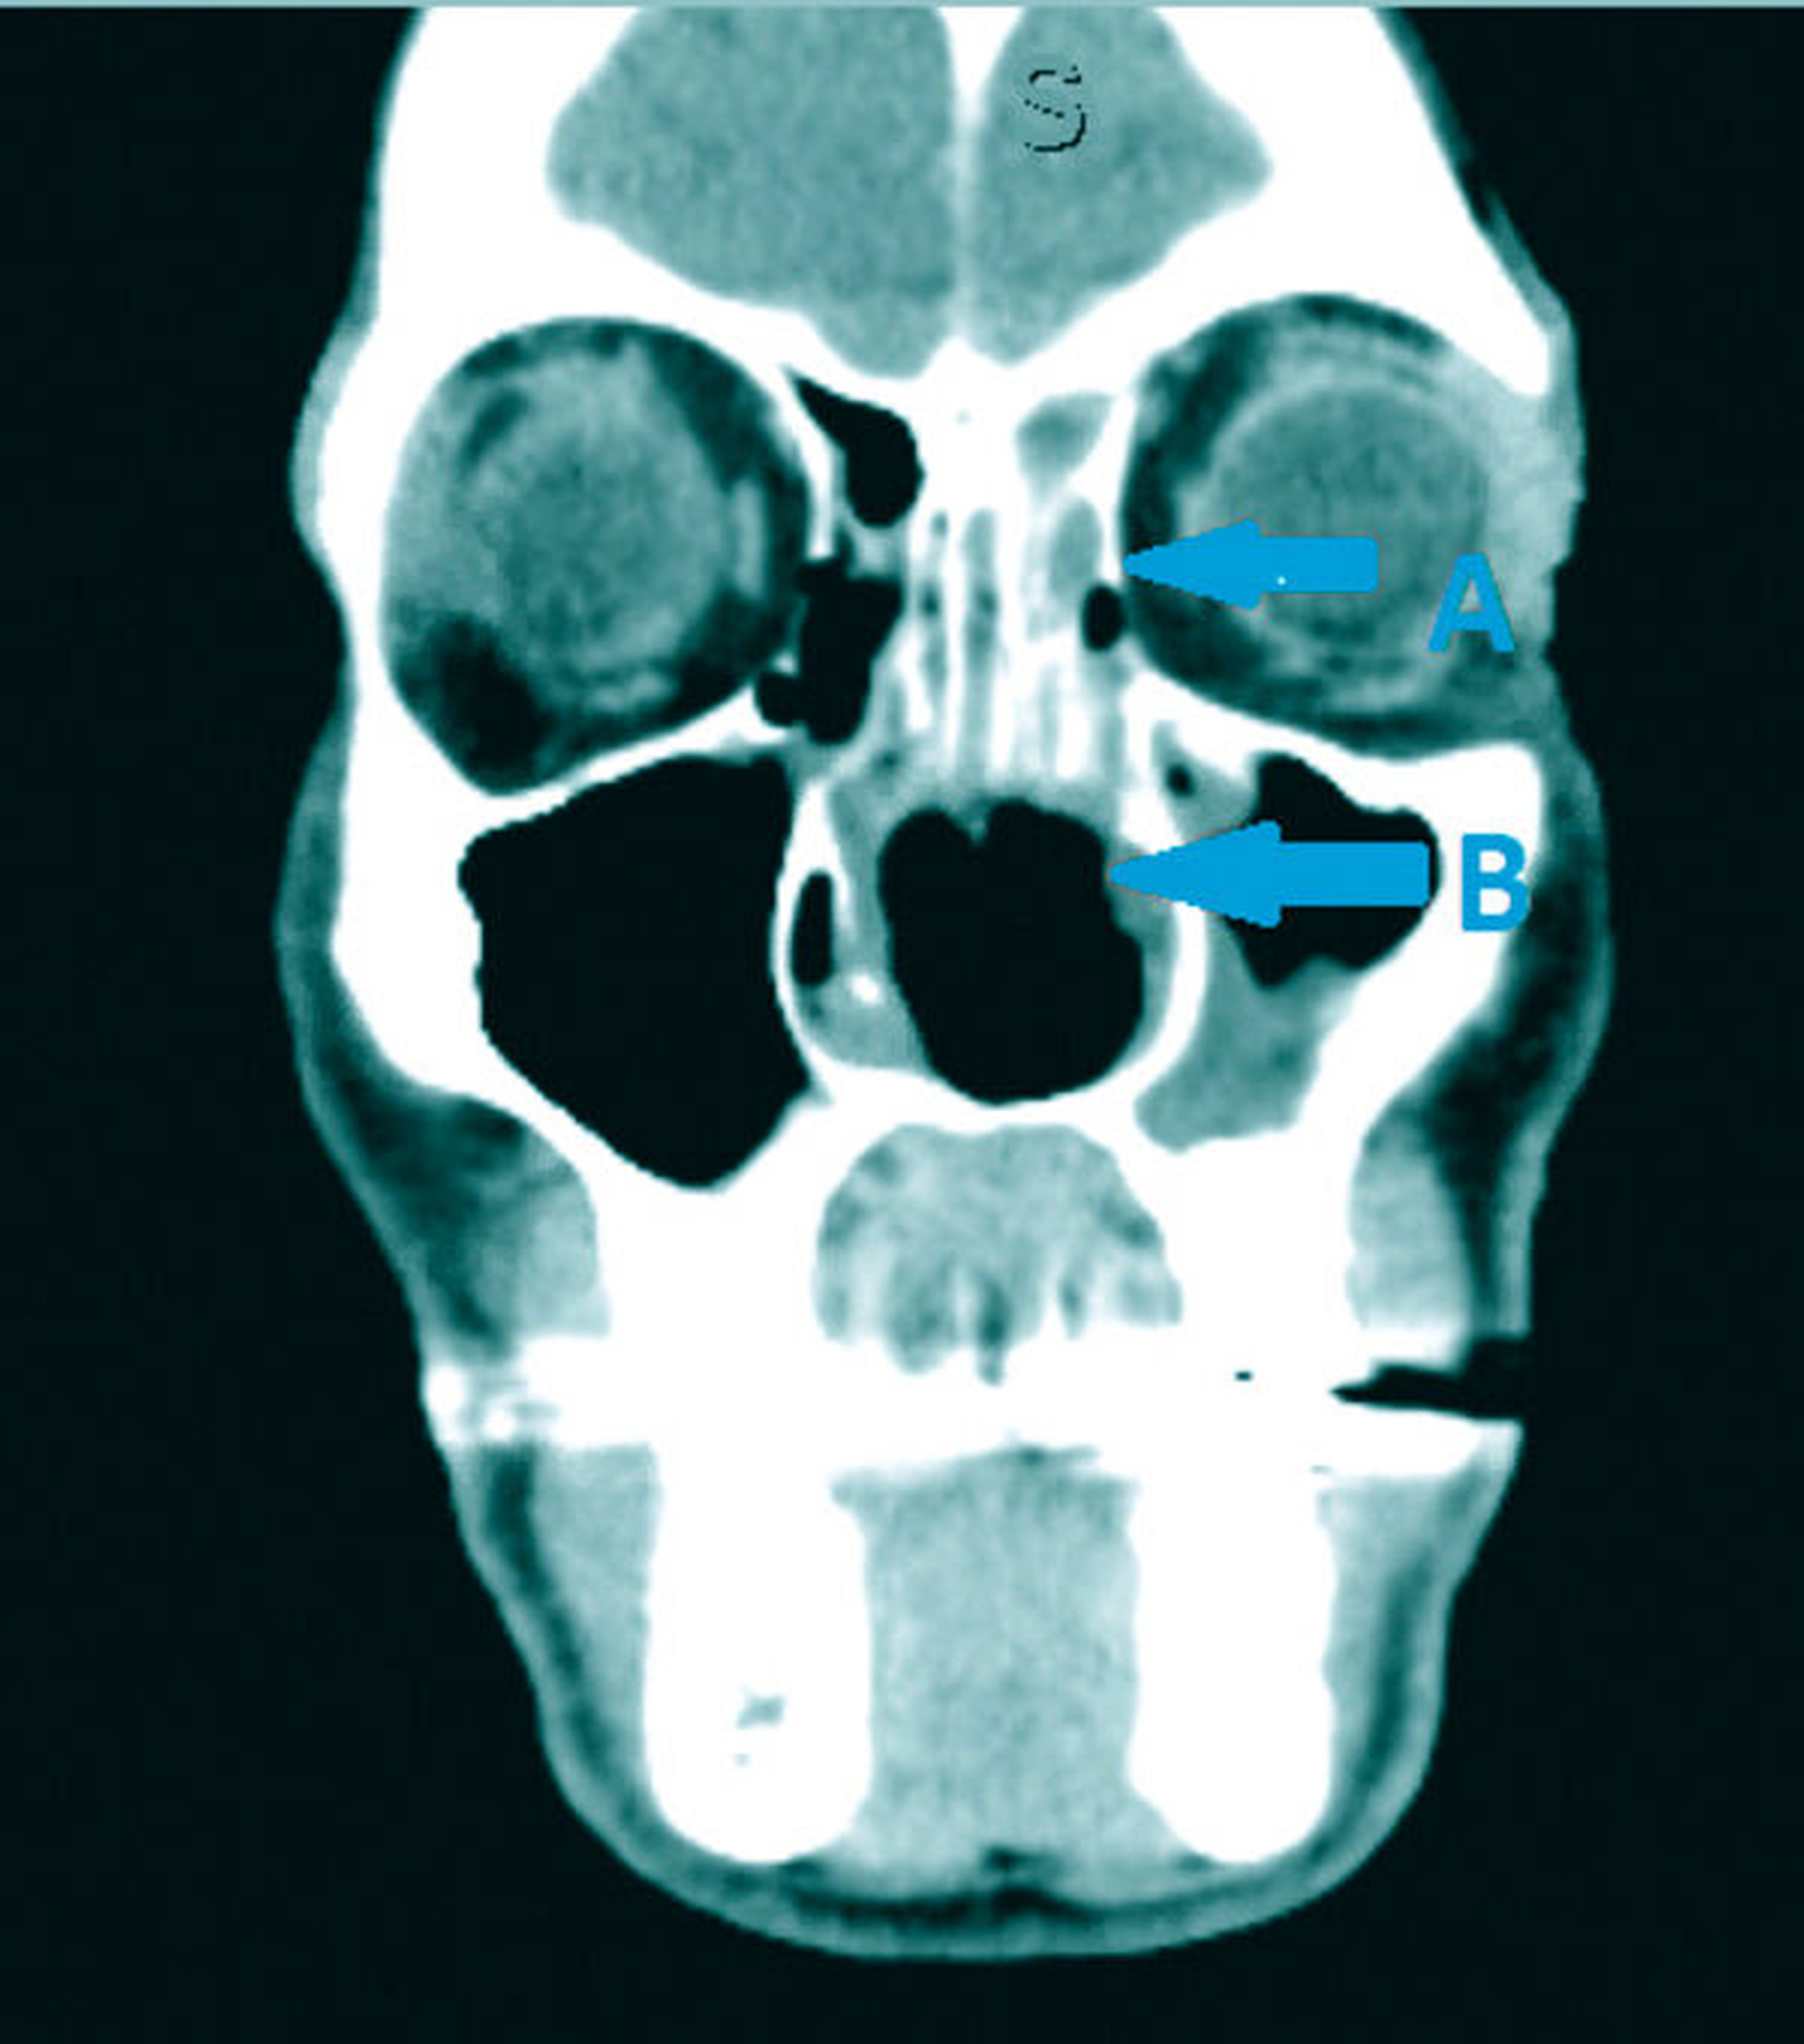

Es folgten eine Blutabnahme mit Routinelabor und Serologie (Lues, HIV, Hepatitis C) sowie eine Alginatabformung zur Herstellung einer Tiefziehschiene. Der Patient wurde zur weiteren Planung und Schieneneingliederung am Folgetag einbestellt. Nach einer raschen CT-Untersuchung mit Kontrastmittel Kopf/Hals (Abbildungen 1 bis 3) erfolgte eine endoskopische Rhinoskopie mit bioptischer Sicherung in ITN unter stationären Bedingungen.

CT-Befund Kopf/Hals: Weichteil-dichte Raumforderung im Bereich der linksseitigen Ethmoidalzellen, vollständige Verlegung des Sinus frontalis links sowie teilweise Verlegung rechtsseitig; zirkuläre Schleimhautschwellung in beiden Sinus maxillaris bei ausgedehnter Destruktion von Nasenseptum, Nasenmuscheln, der medialen Sinuswände und des Hartgaumens sowie subtotal verlegte linke Mastoidzellen bei regelrechter Belüftung vom Mittelohr beiderseits.